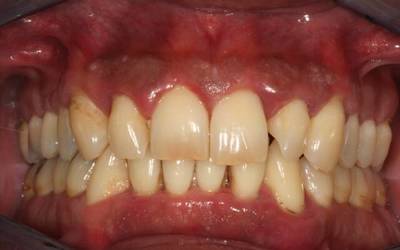

Для течения пародонтита характерны 3 стадии, и симптоматика меняется по мере прогресса заболевания:

- Признаки пародонтита в лёгкой степени совсем незначительны. Дёсны воспалены, в процессе чистки зубов умеренно кровоточат, но без болевых ощущений. Пока не поражена пародонтальная связка, процесс заболевания считается обратимым.

- На средней стадии пародонтита кровоточивость значительно увеличивается, возможны ощущения зуда и жжения. Десна отекает и меняется в контуре, а размер кармана десны доходит до 6 мм.

- Переход в тяжёлую форму пародонтита сопровождается стремительным разрушением костной ткани, зубы теряют опору, веерообразно расходятся и шатаются. На данной стадии заболевания появляется резкий гнилостный запах изо рта, нарушается жевательная функция, и выпадают первые зубы. Глубина кармана десен превышает 6—7 мм.